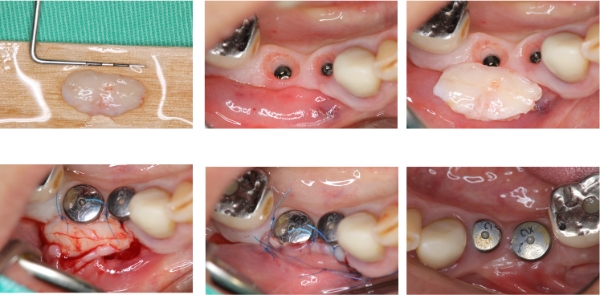

植體植入與補骨

植牙穩定後修補角化牙齦

上面弓與咬合器

咬合器上製作假牙